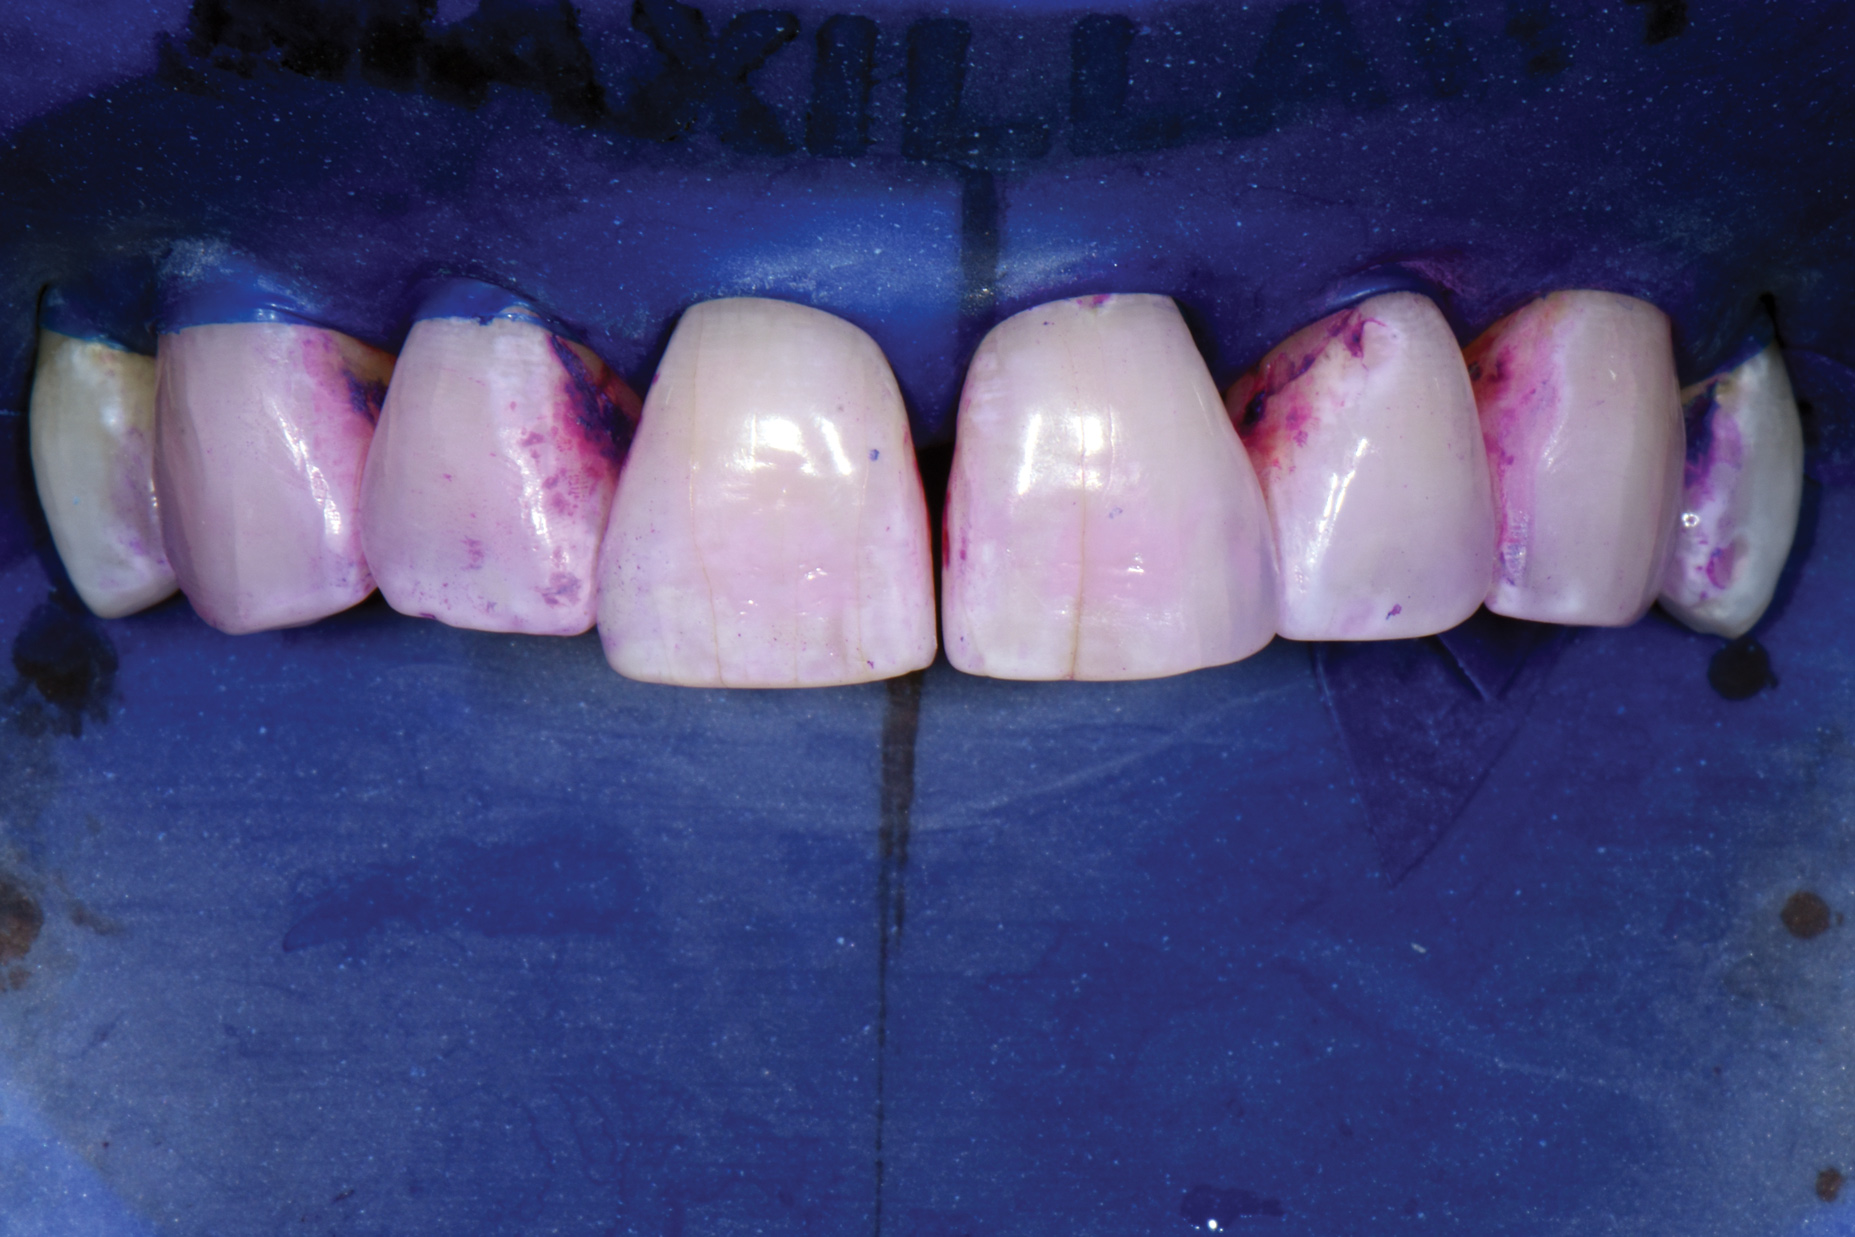

Fig 18. Air abrasion with aluminum trihydroxide to remove biofilm.

Figure 18

Fig 19. Cleaned tooth surfaces after air abrasion prior to application of adhesive bonding resin composite to close black triangles.

Figure 19

Air abrasion with aluminum trihydroxide has been used as an adjunctive for tooth preparation to remove plaque, light calculus, undermined enamel, poorly bonded resins or liners, and soft-tissue tags prior to bonding. The rationale of biofilm removal before bonding is to remove any impediments to effective etching of enamel that may lead to reduced bond strength and microgaps that could contribute to future stain and leakage. Because biofilm can be difficult to visualize, a one-time application of a two-tone disclosing solution to dried teeth may help reveal biofilm and provide a visual cue for effective removal (Figure 17 through Figure 19). Some cleaning particles other than glycine or sodium bicarbonate can alter the enamel surface; therefore, reapplication of disclosing solution should be avoided as this may lead to risk of undesired staining of tooth structure.